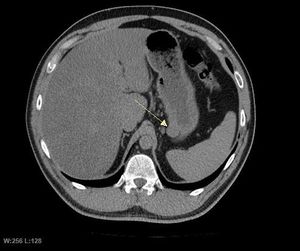

5. 1. 영상 검사

CT 스캔과 MRI는 GIST를 평가하는 데 선호되는 영상 검사 방법이다. 작은 GIST는 대개 점막하 종양 또는 장벽 내 종괴로 나타난다. 바륨 연하 검사에서 이러한 GIST는 인접한 장벽과 직각 또는 둔각을 이루는 매끄러운 경계로 나타나며, 점막 표면은 대개 손상되지 않지만, 50%에서 궤양이 나타나기도 한다. 궤양은 바륨으로 채워져 과녁 또는 표적 병변처럼 보인다. 조영 증강 CT에서 작은 GIST는 균질한 감쇠를 보이는 매끄럽고 선명하게 정의된 장벽 내 종괴로 보인다.큰 GIST는 장 밖으로 튀어나오거나 장 내부로 성장할 수 있으며, 내부에서 괴사(죽음)하여 결국 장 내강과 소통하게 될 수 있는 공동을 형성한다. 공동 형성이 있는 경우, 단순 방사선 촬영에서 종양 내 공기 덩어리가 나타날 것이다. 석회화는 GIST의 드문 특징이지만, 존재할 경우 단순 촬영에서 볼 수 있다.

악성 GIST는 국소 침윤과 전이를 특징으로 하며, 전이는 주로 간, 대망, 복막으로 발생한다. 그러나 뼈, 흉막, 폐, 후복막으로의 전이 사례도 보고되었다. 위 선암종 또는 위/소장 림프종과 달리, 악성 림프절병증 (부어오른 림프절)은 드물며 (<10%) 따라서 영상 검사에서는 림프절 비대가 없는 경우가 많다. 전이가 없는 경우, 악성을 시사하는 다른 방사선학적 특징으로는 크기 (>5 cm), 조영제 투여 후의 불균일한 조영 증강 및 궤양이 있다.[12]